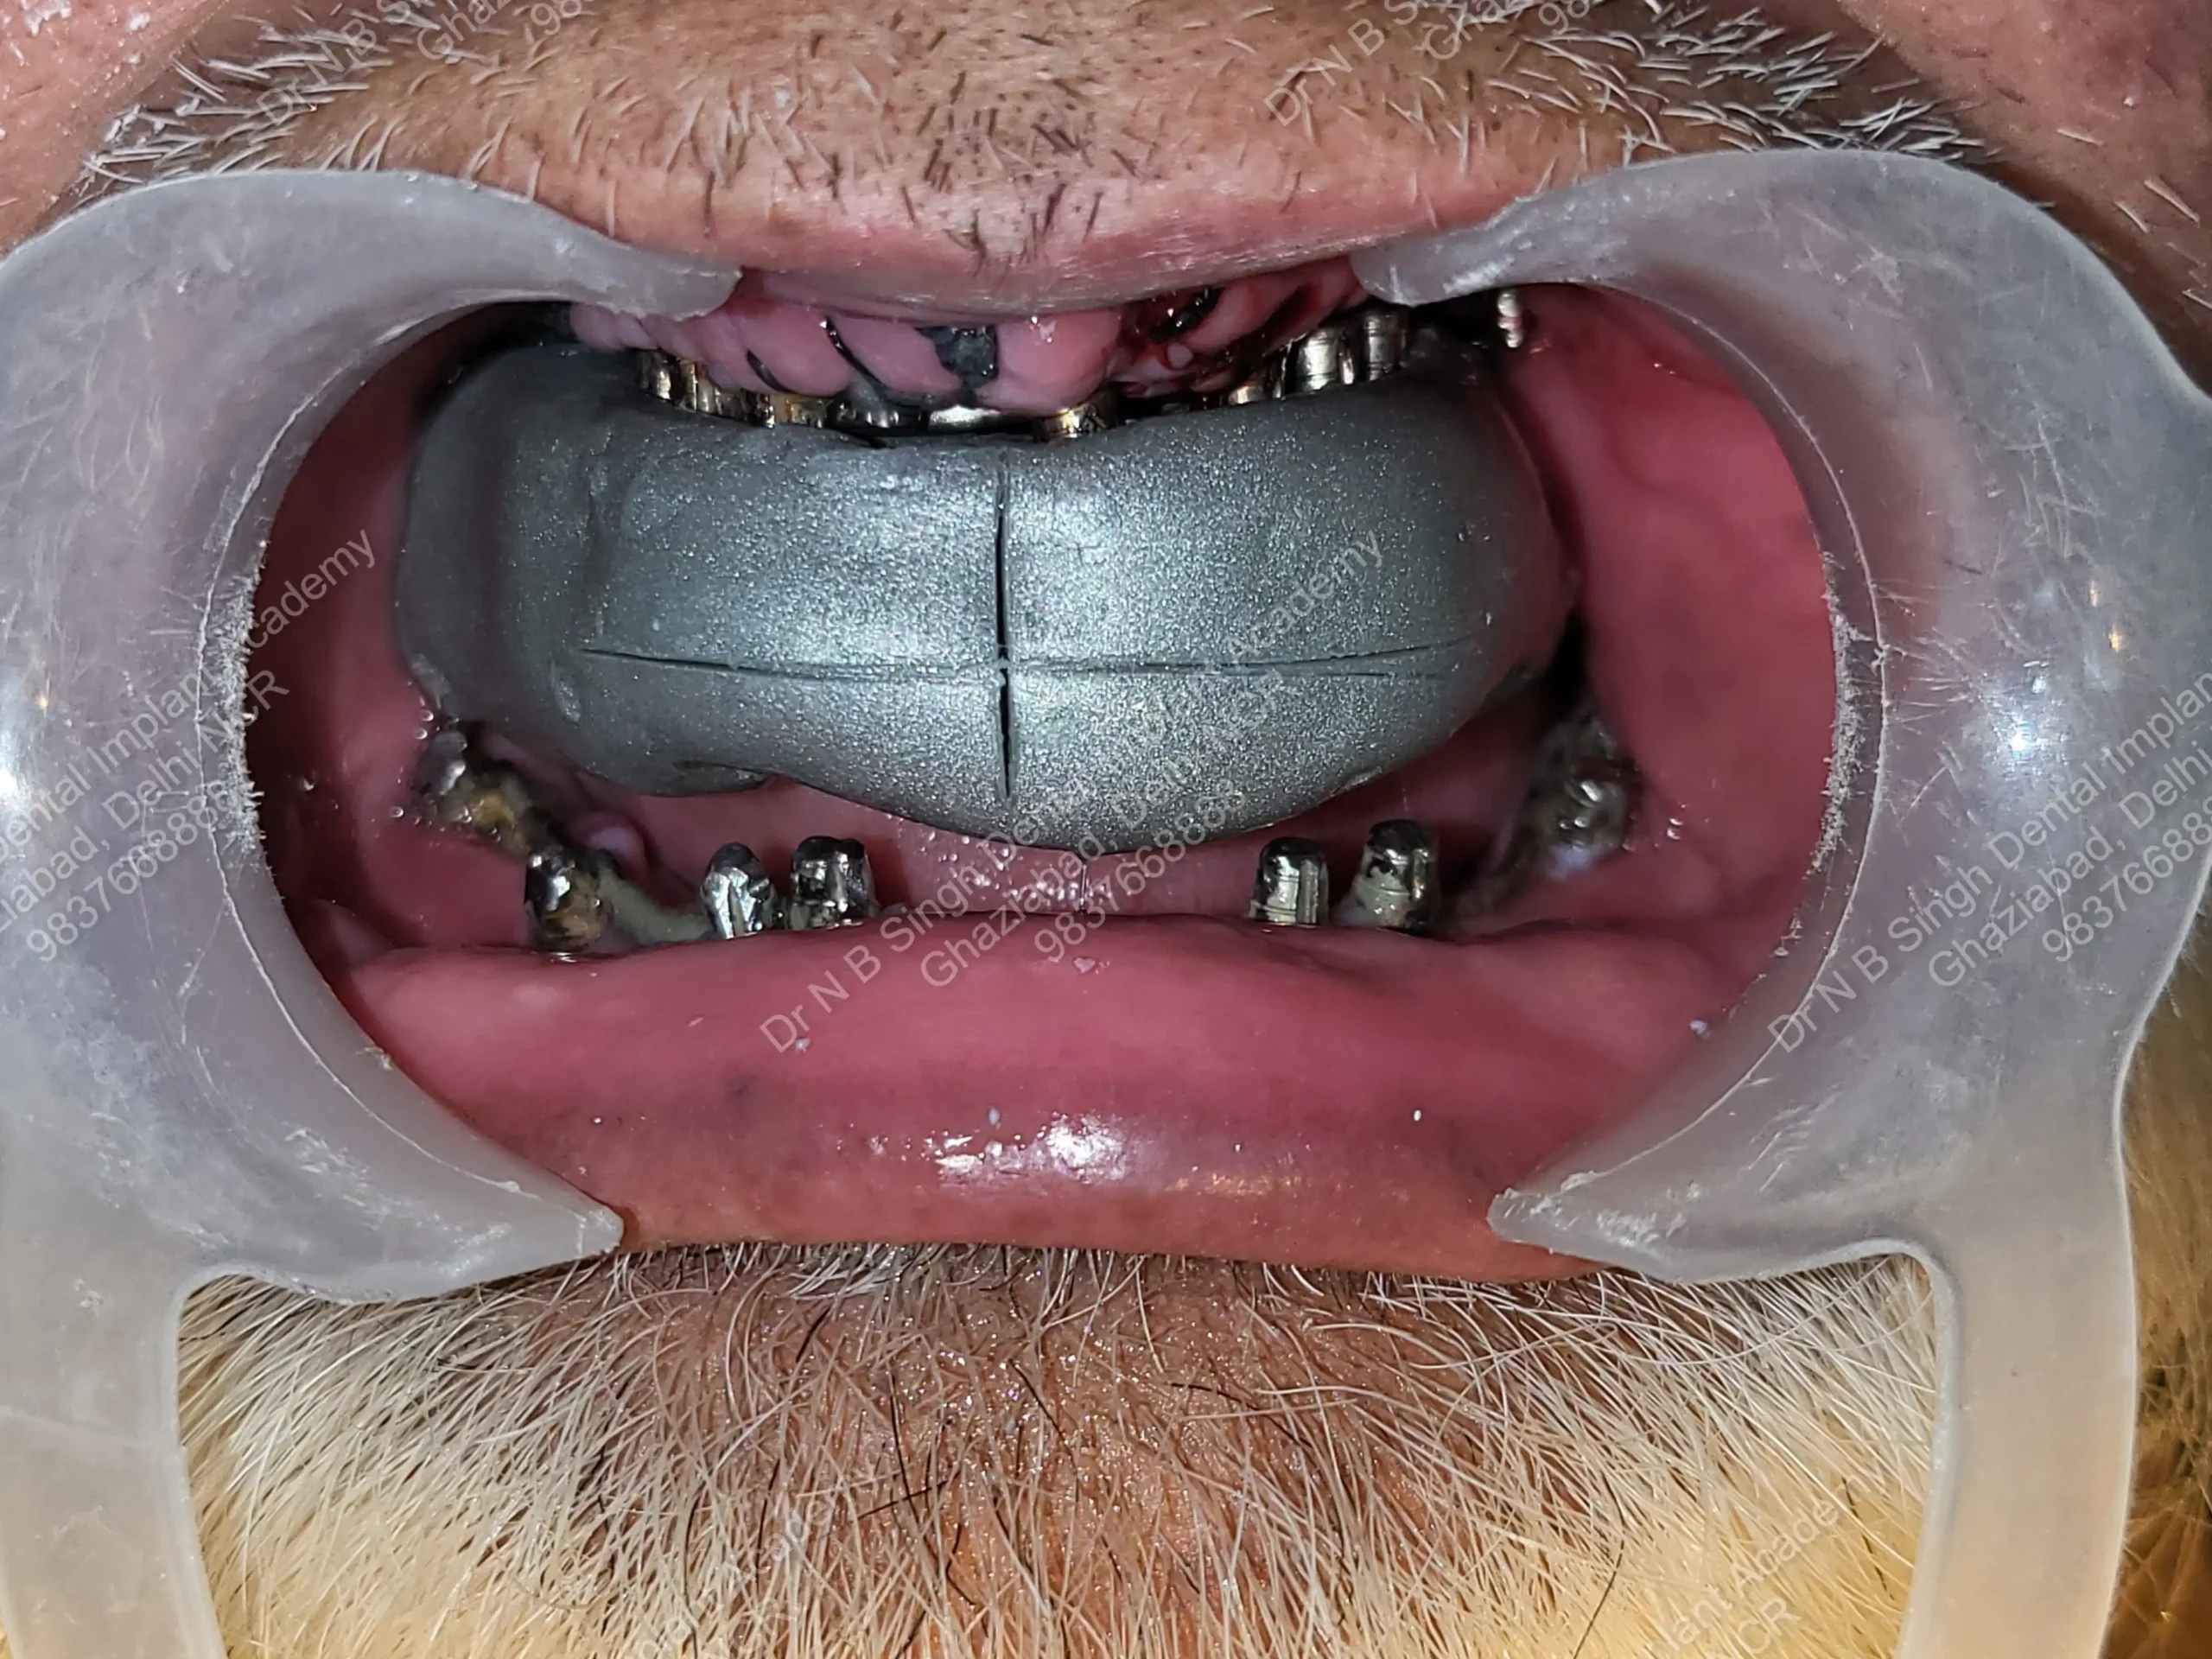

A008 Basal implants – af-qurs 1

Dr. N.B. Singh